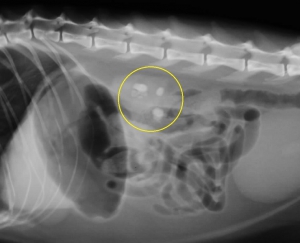

猫でみられた腎結石のレントゲン写真を左下図に示します。その中で「白く見える3つの影」が腎臓(腎盂内)にある腎結石です。イメージしやすいように結石と腎臓の位置関係を右の模式図に重ねてみました。結石は実際には腎臓の腎盂内にあるので外からは見えません。一番左の結石は尿管に落ちかかっています。